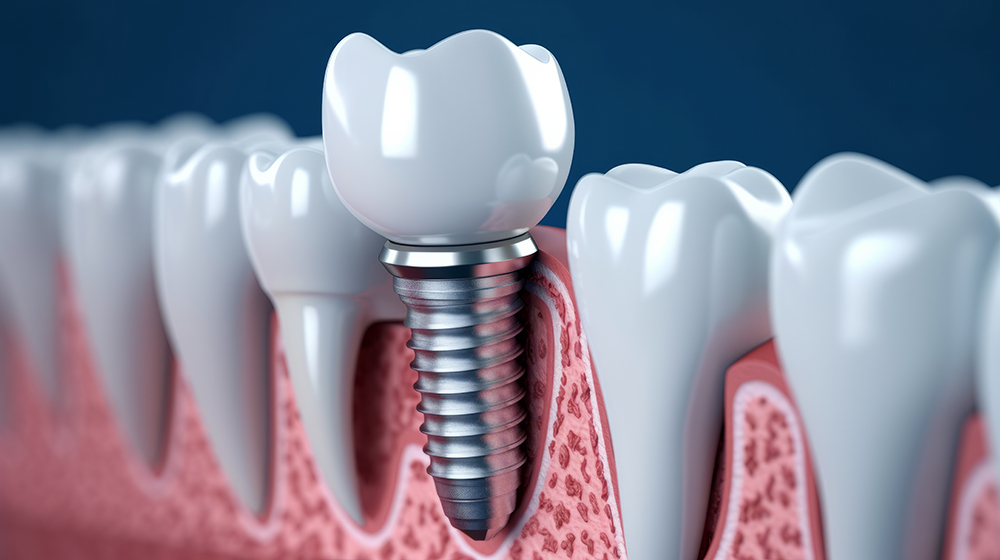

본격적인 임플란트 식립 과정에서는 치조골에 인공치아 뿌리(임플란트)를 심습니다. 이 과정은 국소마취를 하며, 수술 시간은 보통 한 개당 30분에서 1시간 정도 걸립니다. 수술이 끝나면 잇몸을 봉합하고, 임플란트가 뼈에 완전히 결합될 때까지 기다려야 합니다.

임플란트가 뼈와 단단히 결합하는 과정을 '골유착'이라고 부릅니다. 이 기간은 약 3개월에서 6개월이 필요하며, 뼈 상태에 따라 다를 수 있습니다. 골유착이 잘 이루어져야만 임플란트가 안정적으로 자리잡고, 정상적인 기능을 수행할 수 있습니다.

골유착이 완료되면 임플란트 위에 지대주(어버트먼트)를 연결하고, 그 위에 보철물을 부착합니다. 이 과정에서 환자 맞춤형 치아 모양을 디자인하고 제작하며, 자연치아와 최대한 유사하게 보이도록 조정합니다. 최종적으로 임플란트 보철물을 설치하며, 이로써 전체 시술이 마무리됩니다.